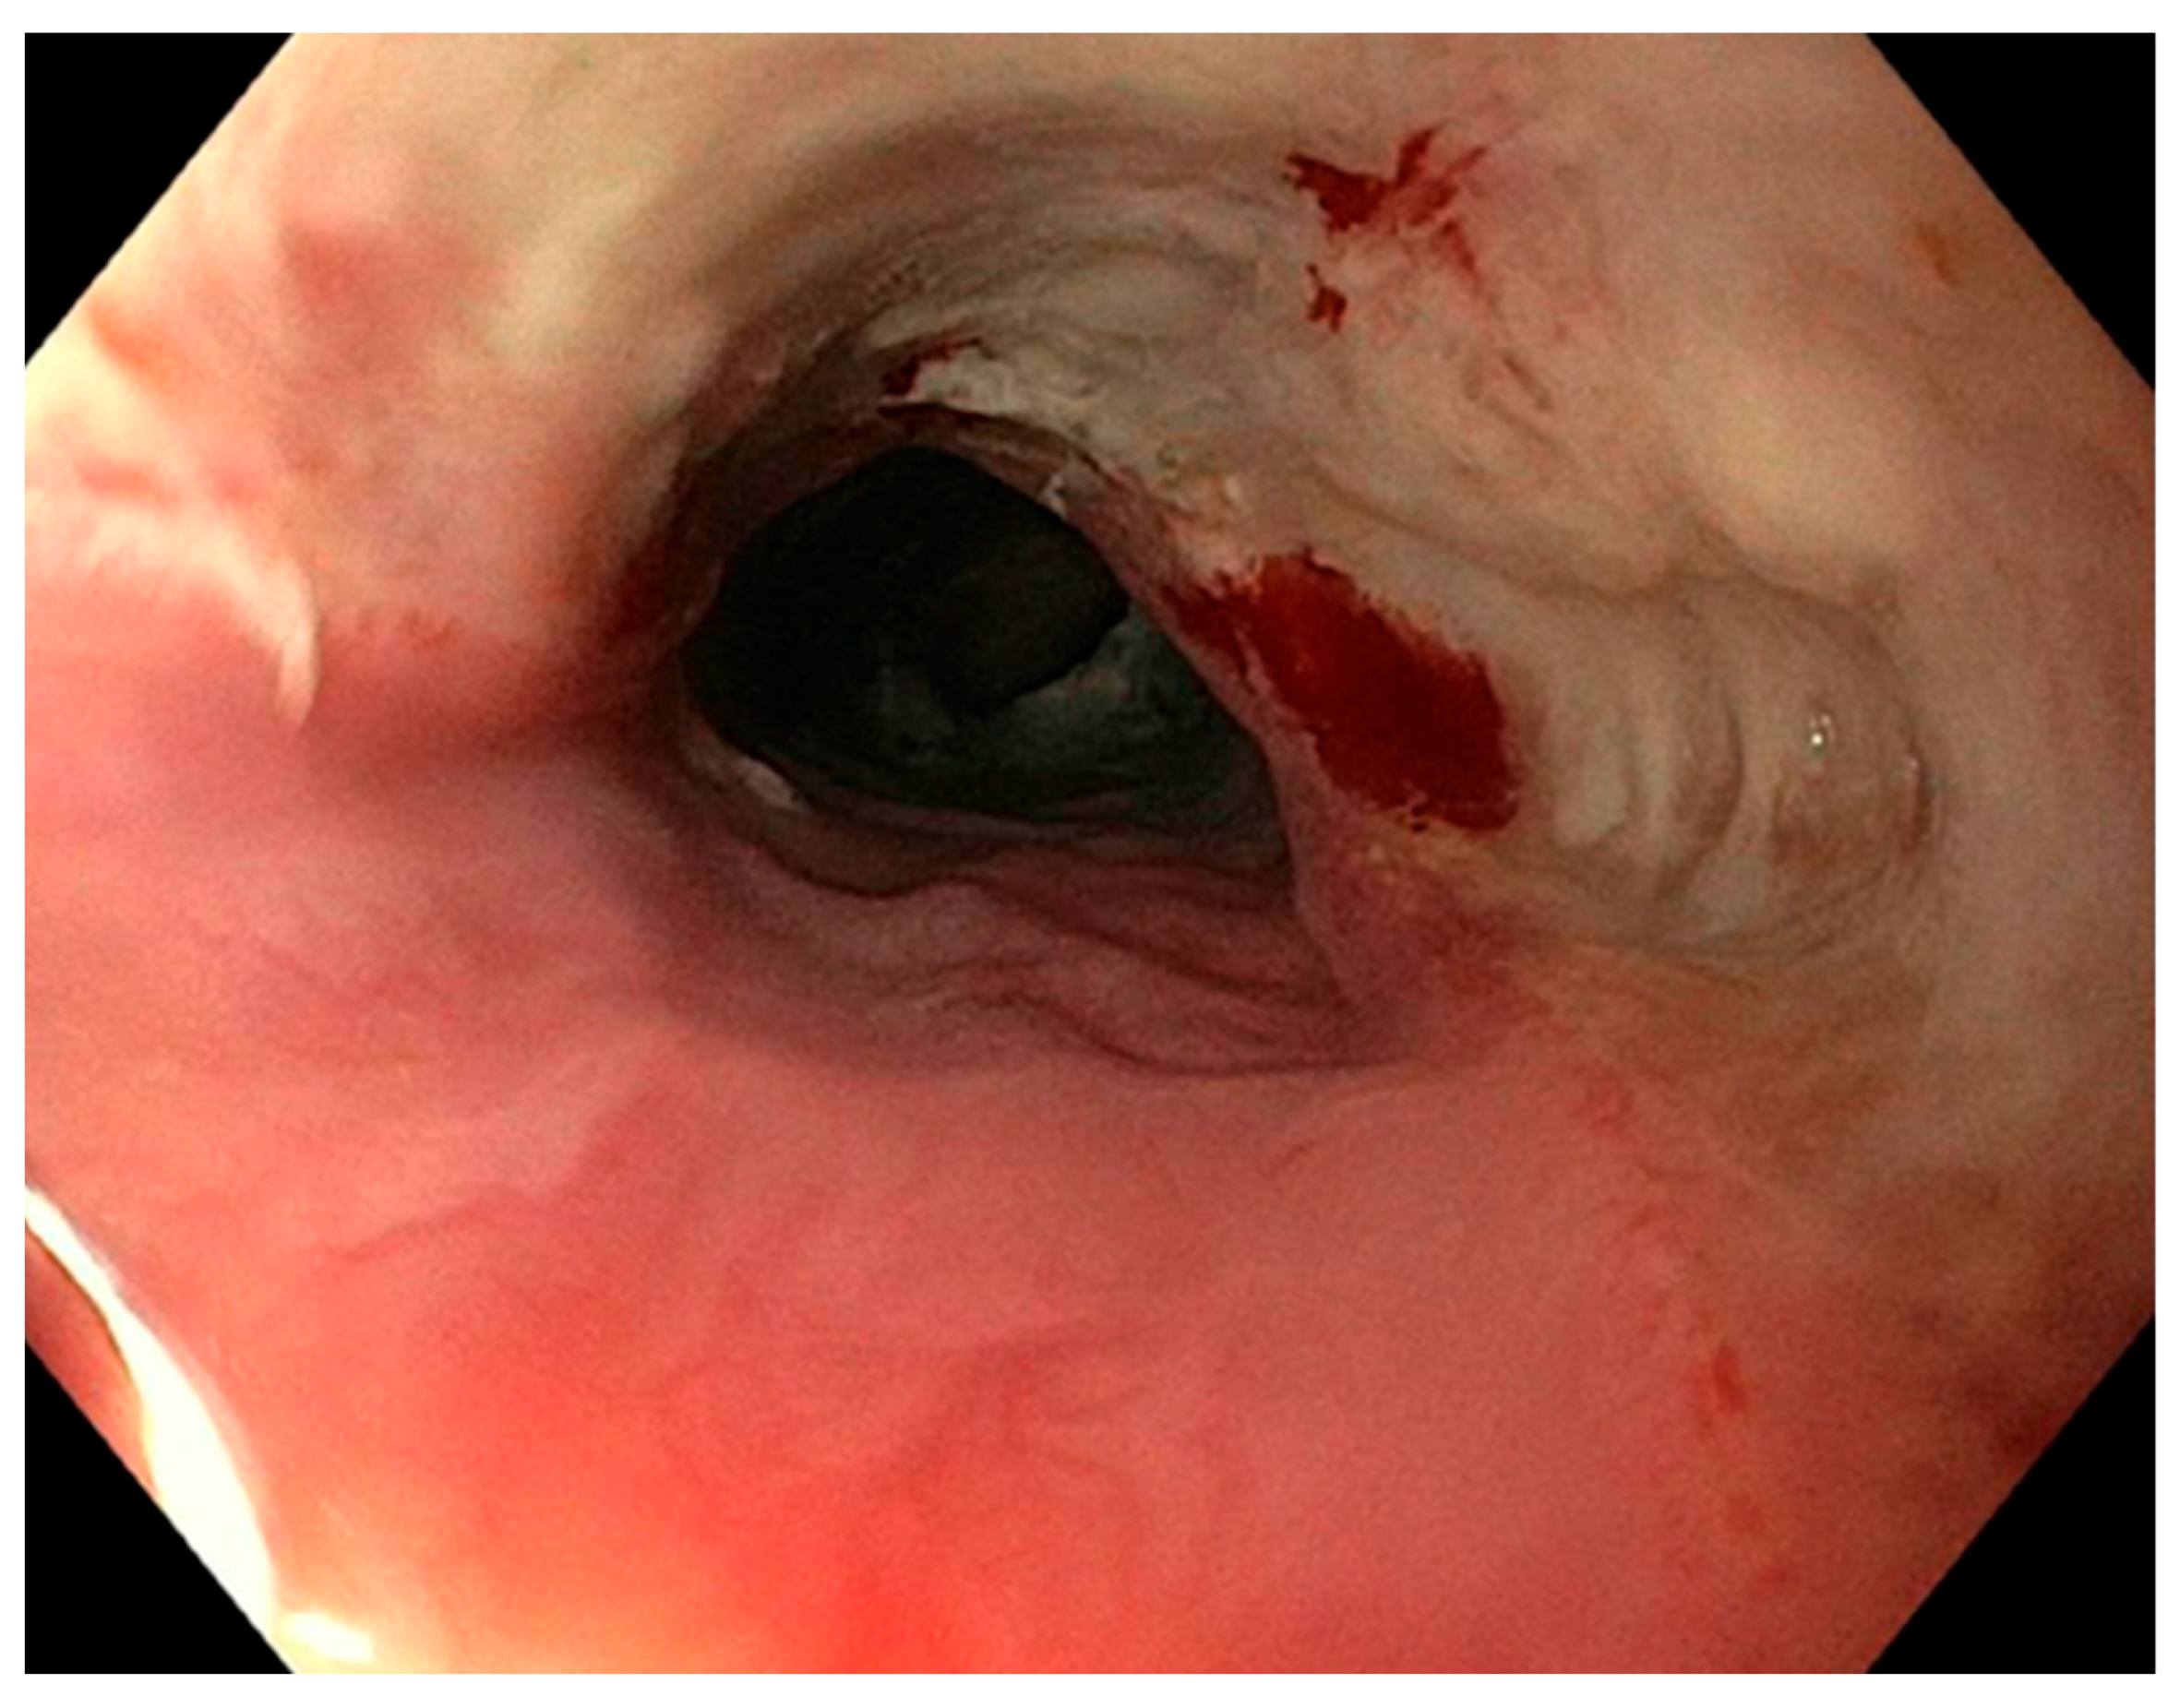

2.2. Diagnosis and Symptoms